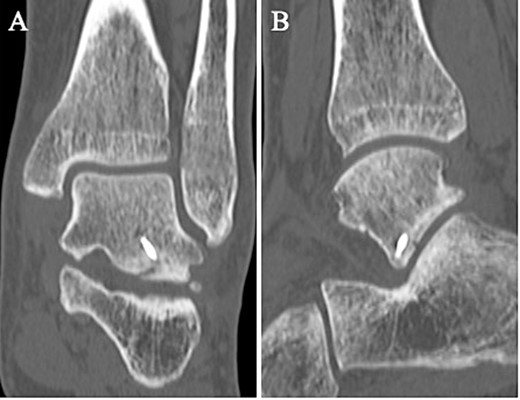

A 24-year-old male basketball player presented to our hospital complaining of left lateral ankle pain during a cutting motion. His height, weight, and body mass index were 172 cm, 64.0 kg, and 21.6 kg/m2, respectively, and he had no history of previous medical conditions. On his first visit to our hospital, he could not walk due to pain. Physical examination revealed swelling, ecchymosis, and tenderness at the lateral aspect of his left ankle. The American Orthopedic Foot and Ankle Society (AOFAS) score was 32 out of 100 points. Plain radiographs of the left ankle showed no abnormal findings in the anteroposterior view, but a fracture line was discovered at the base of the lateral process of the talus in the lateral view (Fig. 1). Non-contrast computed tomography (CT) showed a simple fracture line that extending from the talofibular articular surface down to the posterior talocalcaneal articular surface of the subtalar joint. In addition, the bone fragment was displaced >2 mm (Fig. 2). The patient was diagnosed with Type I LPFT and underwent surgical treatment.

Non-contrast CT showed a simple fracture line that extending from the talofibular articular surface down to the posterior talocalcaneal articular surface of the subtalar joint in the coronal (A) and sagittal (B) views.